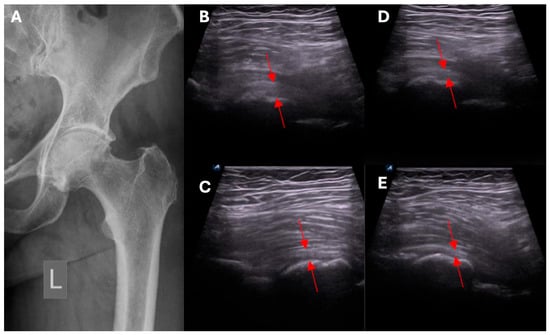

- Ultrasound assessment of hip morphology, and radiologic imaging with MRI where necessary.

- Clinical and ultrasound assessment to identify local pathological mechanisms underlying symptomatic HOA.

- Exclusion/confirmation of intracapsular and extracapsular inflammation based on ultrasound imaging.

- Clinical and ultrasound assessment of the intracapsular, extracapsular, anterior, anteromedial, lateral, and posterolateral aspect of the hip.